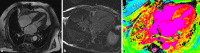

Amyloidosis is a rare but life-threatening protein misfolding disease. The early diagnosis and enrollment of patients into multicentre trials is of great importance, as is the need for intensive collaboration between multiple medical departments and experienced specialists. In the following review, the most interesting abstracts from the annual American Society of Hematology (ASH) meeting in 2016 are presented. The topics include the limitations of established biomarkers in risk assessment and response evaluation, the introduction of a new biomarker, the comparison of different treatment sequences and the efficacy of a multiple drug regimen in light-chain (AL) amyloidosis.